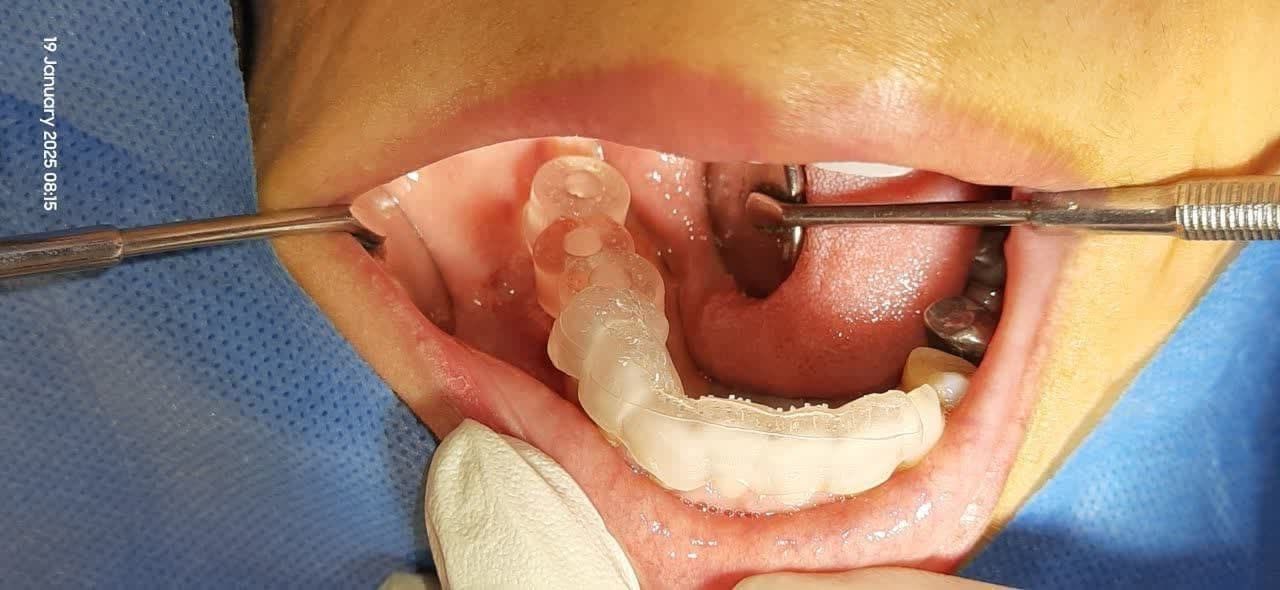

بي دنداني خلفي فک پايين

راهنماي جراحي ساخته شده به روش ديجيتالي با استفاده از سي تي اسکن بيمار و اسکنر داخل دهاني

تصوير راهنماي جراحي ساخته شده به روش ديجيتالي